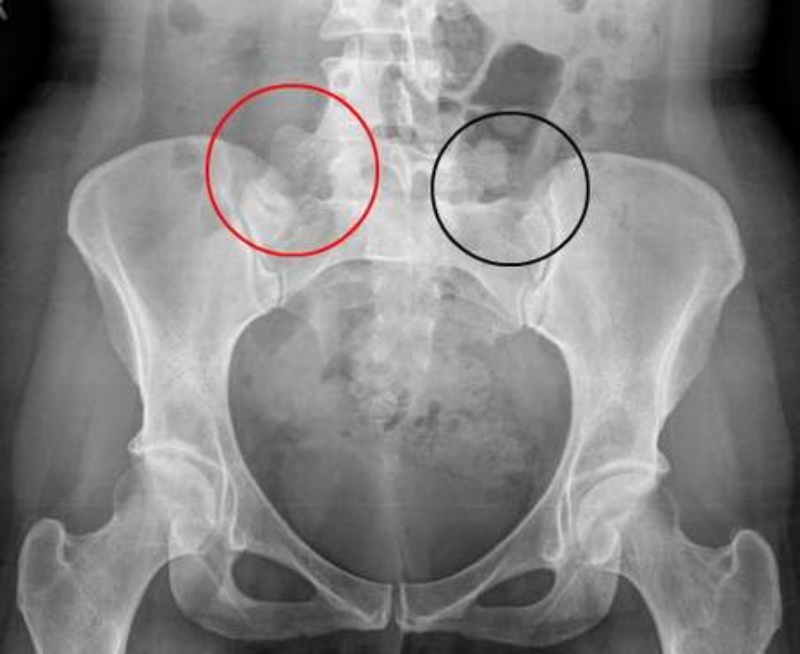

Hình ảnh CT viêm khớp cùng chậu

Hình ảnh chụp CT cho thấy gai xương xuất hiện ở rìa trước kèm tình trạng xơ cứng dưới sụn ở bên trái